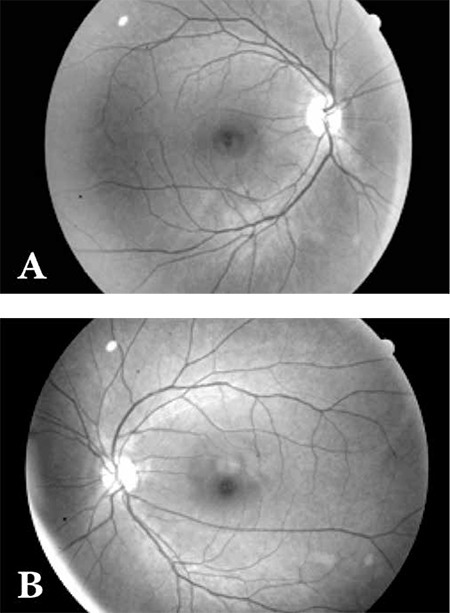

- 안저검사: DR-like 소견

- FAG: 비관류 영역, 미세동맥류 누출, NV

- 미세동맥류, 점상출혈, 면화반

- 경성삼출물

- 모세혈관 비관류

- 황반부종

- 신생혈관 → VH → TRD

- 방사선 조사 범위에 일치하는 소견이 특징